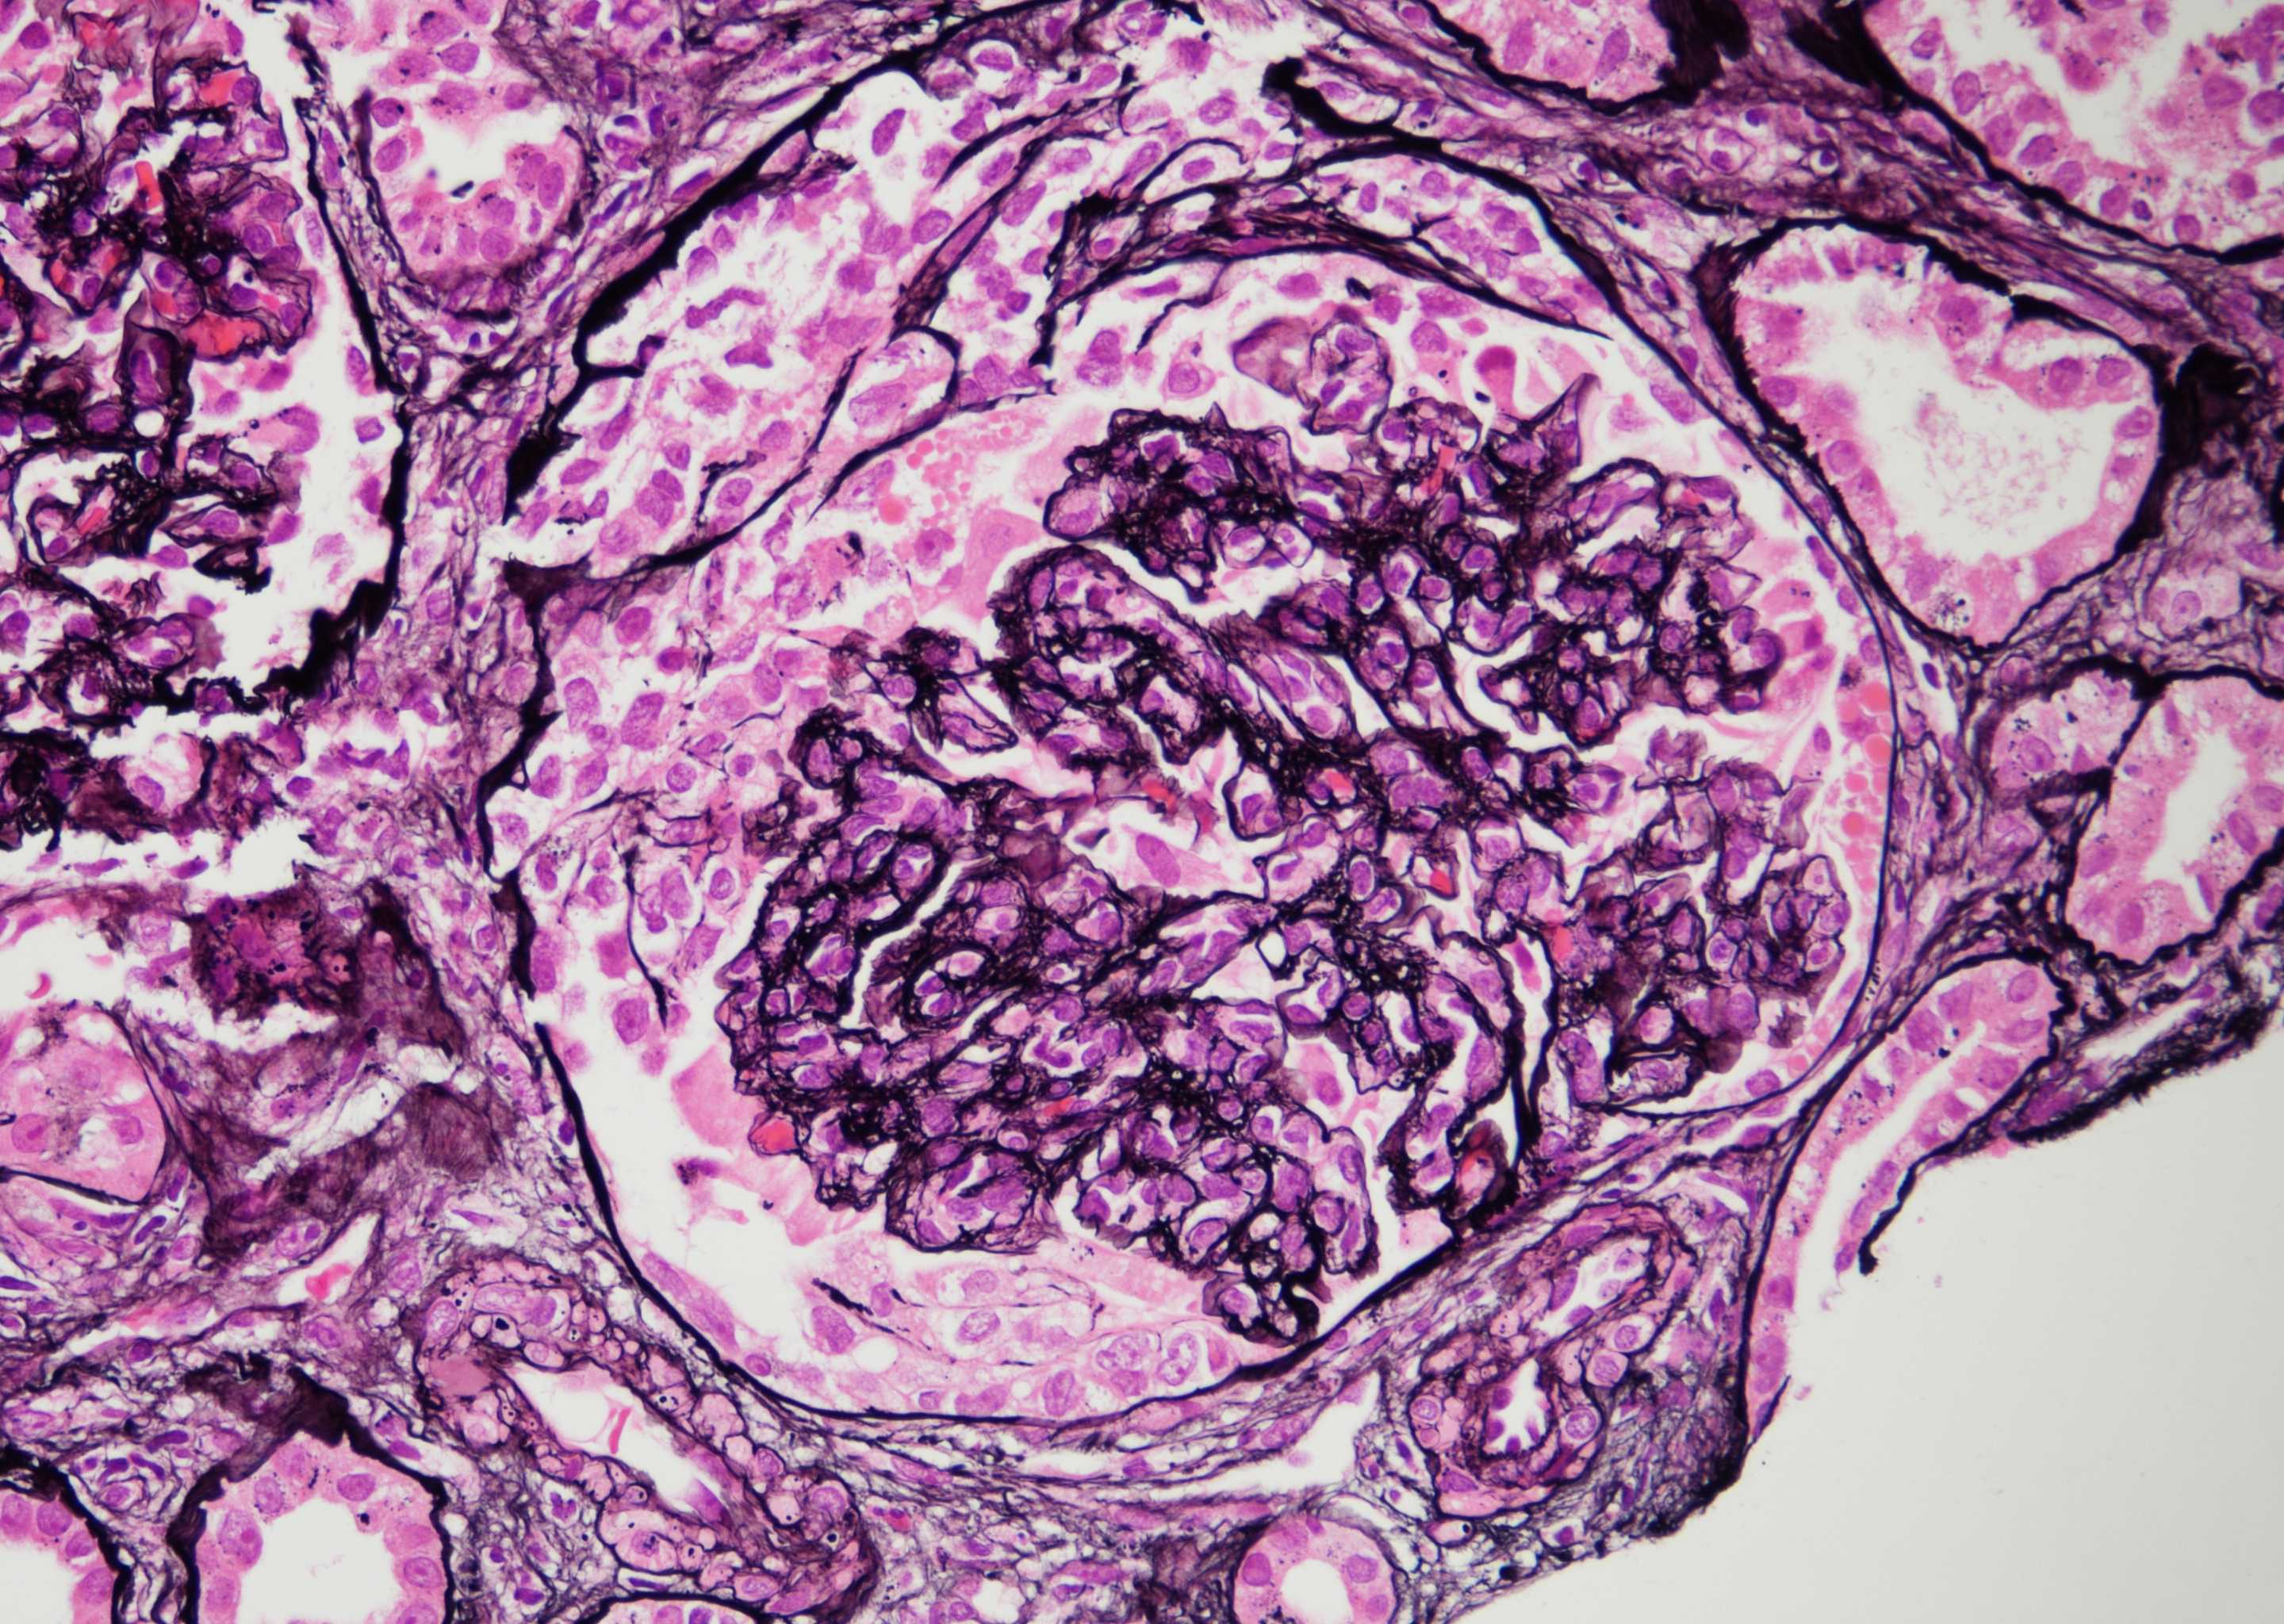

Results: Work up was notable for bartonella henselae bacteremia. He underwent an allograft biopsy that demonstrated post-infectious glomerulonephritis (GN); Mycophenolate was discontinued and treatment was started with rifabutin and doxycycline. AKI initially improved, but later worsened and a second biopsy was performed, which revealed a pattern of diffuse suppurative proliferative GN (Fig.1) with focal crescents (Fig. 2). Electron microscopy revealed sub-endothelial and sub-epithelial electrondense immune deposits. The immune deposits were predominantly IgA, IgM and C3, and negative for IgG. He was started on IV steroid pulse and initiated on dialysis for worsening volume overload. Four weeks after discharge a follow-up biopsy was performed as the patient remained on dialysis. The biopsy showed a focal proliferative GN with more segmental intra-membranous immune deposits and rare sub-epithelial humps, a pattern consistent with resolving post-infectious GN. Soon after he came off dialysis with resolving acute kidney injury.